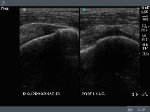

Supraspinatus Tendon transverse axis: note the dark hypoechoic rim above the cortical surface (articular cartilage), this indicates the probe position is over the proximal Supraspinatus

Distal Supraspinatus at its insertion, note the hypoechoic rim above the cortex is absent, image is now over the Greater Tuberocity. The defect in the tendon on this image is at the anterior margin of the tendon at the border of the biceps tendon.